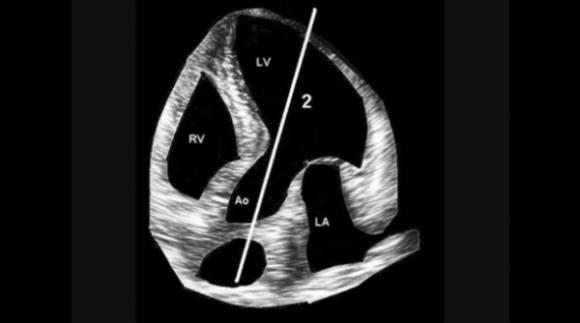

La auscultación Doppler presenta información audible que no da la auscultación clásica, por ejemplo, la apertura de válvulas cardíacas, el movimiento de la válvula mitral, la apreciación de la función diastólica a través de la audición de la entrada de sangre en el VI, la auscultación de venas de tórax como la VCS y VCI, la auscultación de arterias y venas del abdomen o la auscultación de la arteria pulmonar. Además de presentar información más fácilmente detectable en insuficiencias y estenosis valvulares y se puede auscultar en ambientes muy ruidosos, ya que no es afectado por el ruido ambiente.